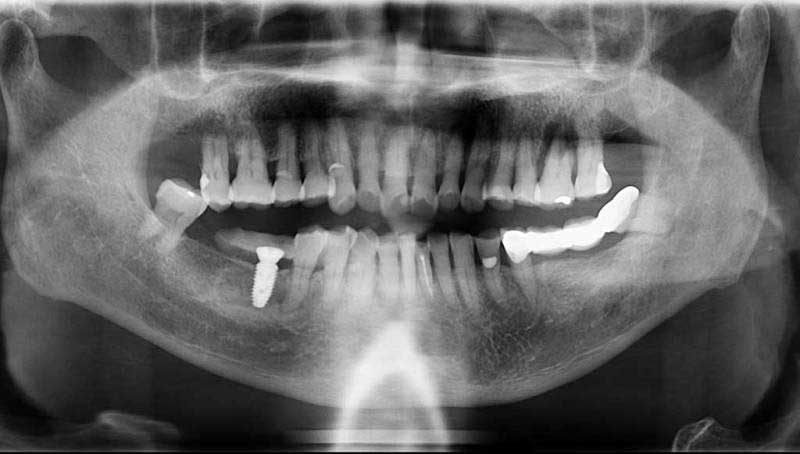

案例2